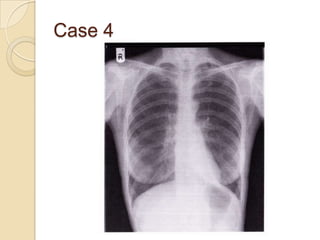

Case 4

   Left lower lobe

collapse

◦ Left lower lobe

collapses behind

heart

◦ Heart shadow

appears whiter

◦ Double left heart

border (sail sign)

◦ Left hemidiaphragm

border can’t be

followed to spine

Case 4  Left lower lobe collapse ◦ Left lower lobe collapses behind heart ◦ Heart shadow appears whiter ◦ Double left heart border (sail sign) ◦ Left hemidiaphragm border can’t be followed to spine